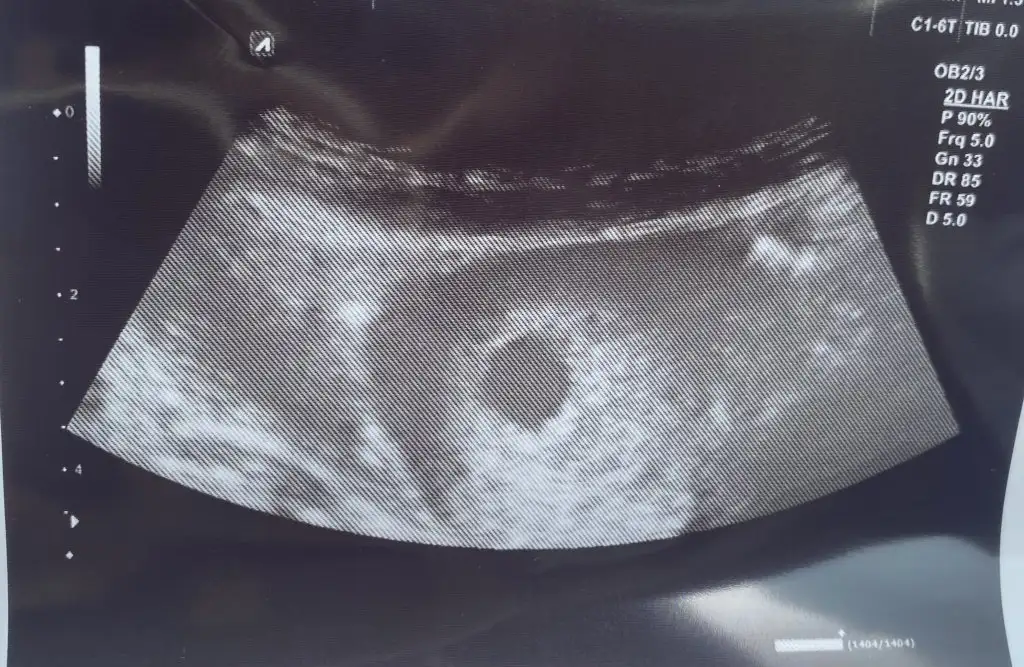

İlk Ultrason görüntüsü 6+5 karından. İkincisi ise 8+5 yine karından Ultrason. 11+6 da nasipse ikili teste gidicez belki doktor bir tahminde bulunabilir ama sizinde görüşlerinizi merak ediyoruz![]()

Kuzum hiç anlamam sadece içimden geçeni söylüyorum kız gibi geldibu da benim minnoş

ilki 6 haftalık silik olan 8![]()